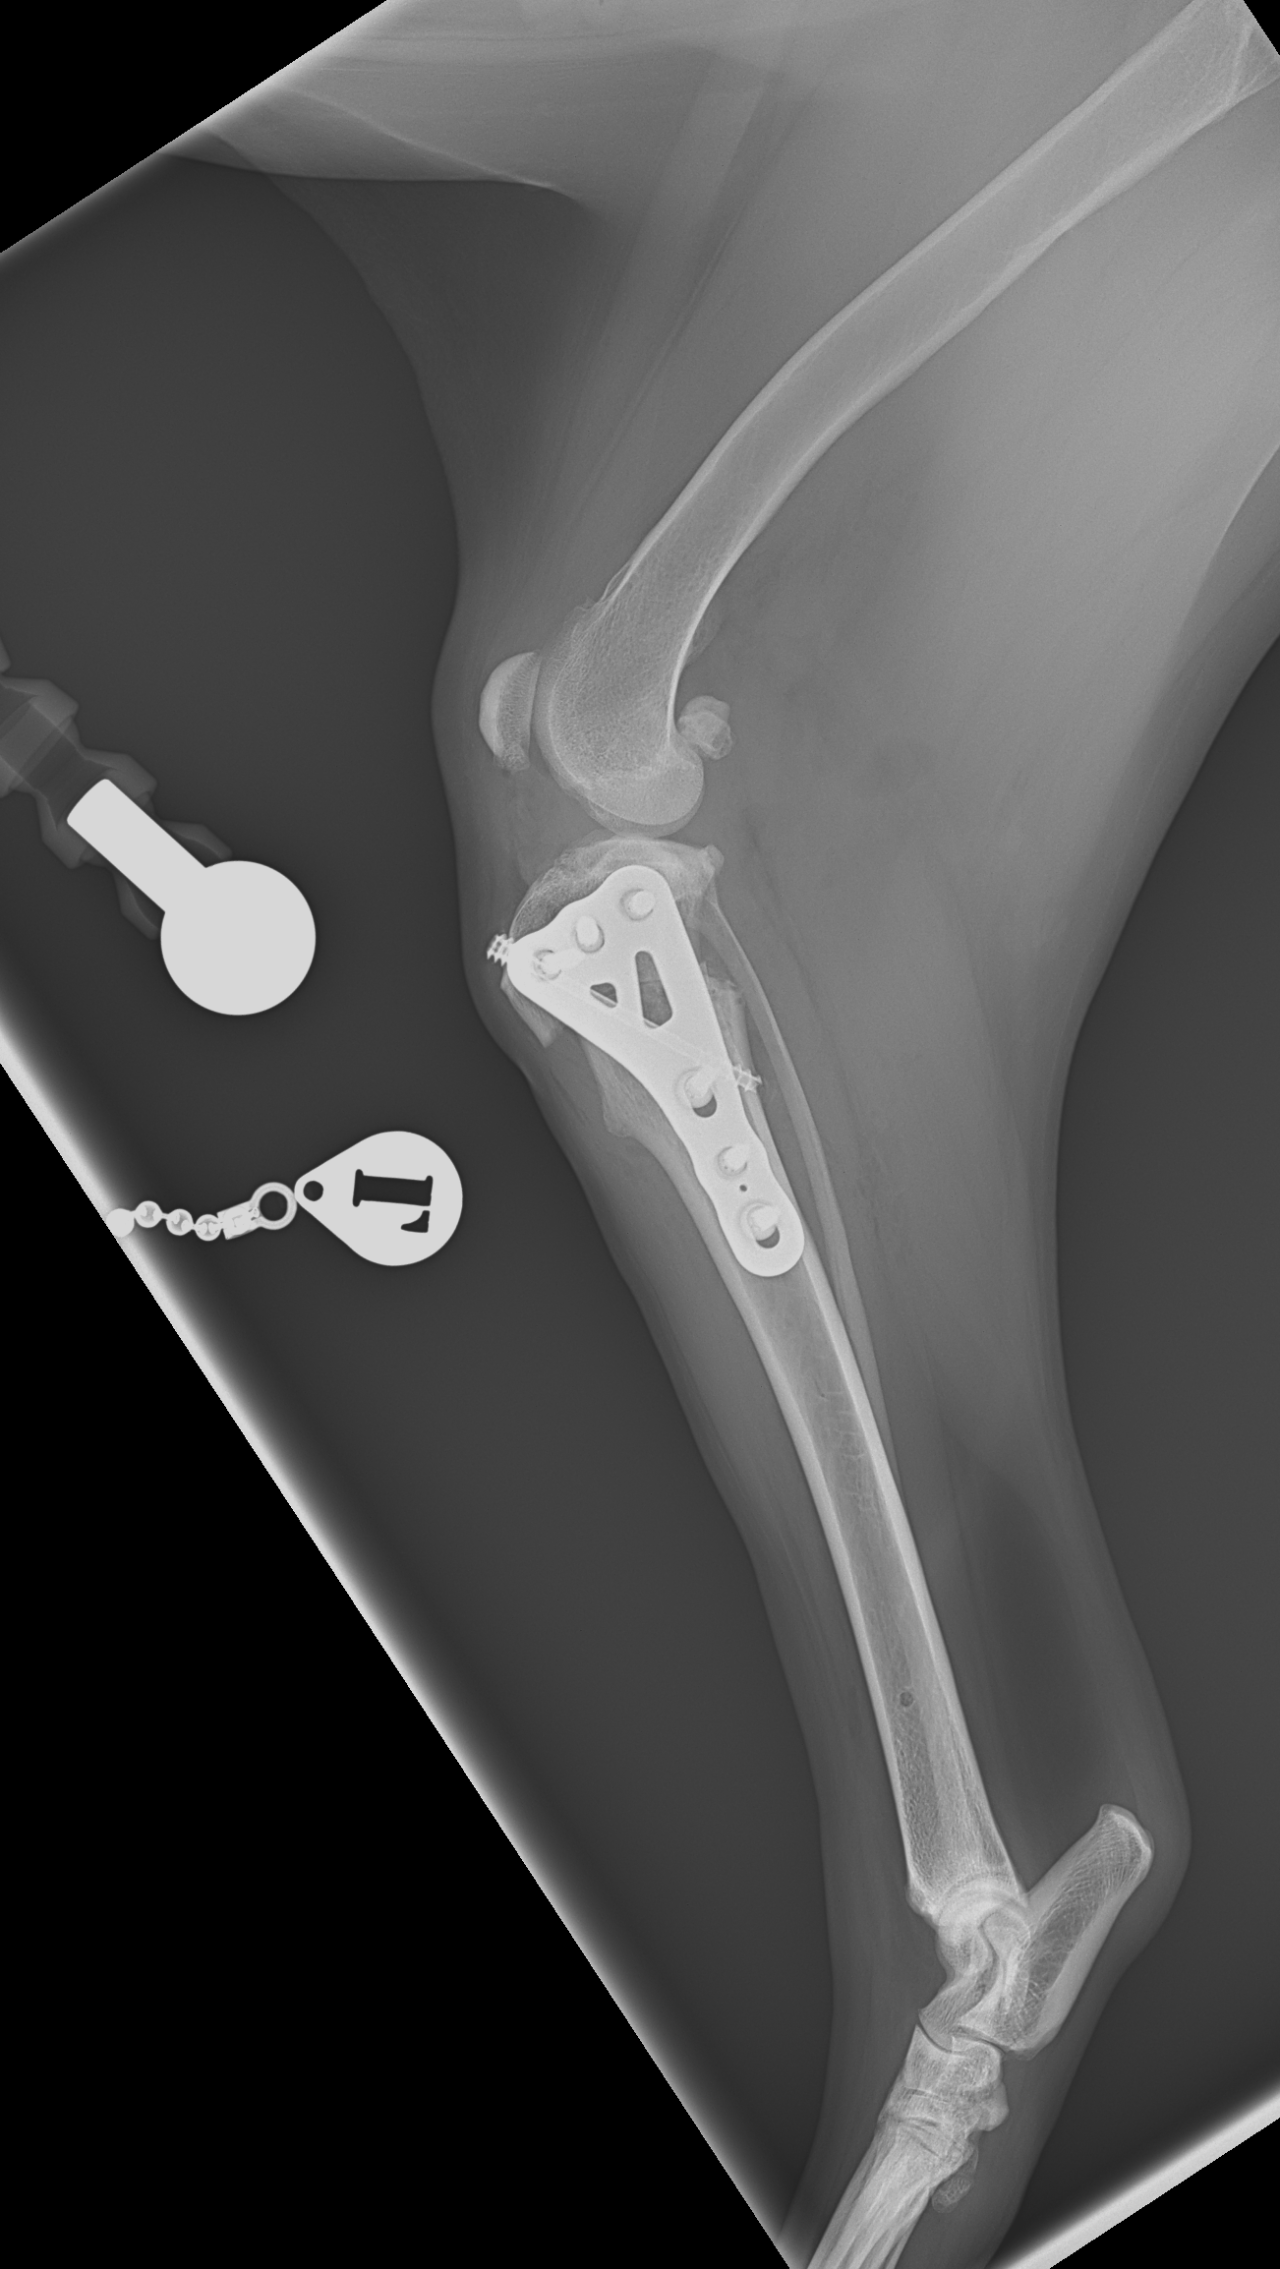

CBLO #244

大型犬の前十字靭帯疾患(慢性)に対して膝関節の力学的な安定化を目指しでRita 3.5 CORA Based Leveling Osteotomy+ヘッドレス・コンプレッションスクリューで固定しました。しばらくは安静が必要です。